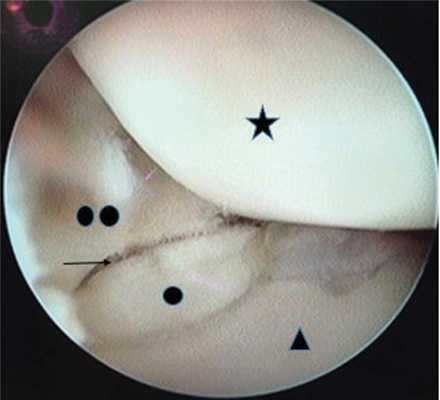

Визуализировали зону ложного сустава (рис. 2). Рис. 2. Артроскопическая анатомия среднезапястного сустава. Звездочкой обозначена ладьевидная кость (scaphoid); треугольником — полулунная кость (lunate); один круг — проксимальный фрагмент ладьевидной кости (the proximal pole of the scaphoid); два круга — дистальный полюс ладьевидной кости (the distal pole of the scaphoid); стрелка — ложный сустав ладьевидной кости (scaphoid pseudarthrosis).